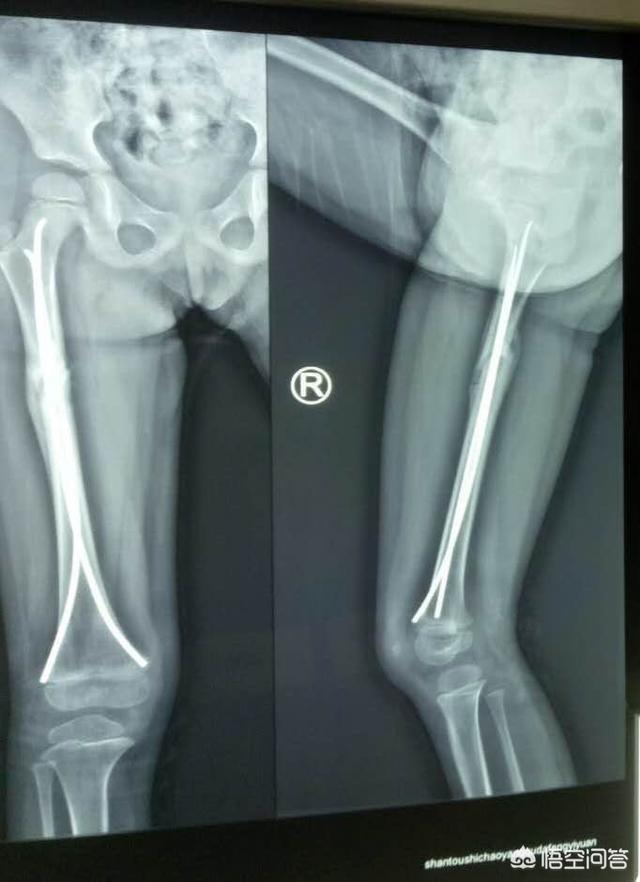

腿受伤打了钢钉要多长时间才能把钢钉取出来?

儿童骨折后如果手术,大多数采用微创方法,用克氏针固定,也有螺钉,弹性髓内钉,钢板极少用,孩子生长快速,大多数在三个月左右骨折就长得很结实,也可以取出内固定物了。

国外专家建议取出内固定器材的时间分别为:胫骨大约1年,股骨大约2年,前臂骨及肱骨大约1.5-2年,个别手术风险大,或高龄病人,也可不拆除,长期观察即可。